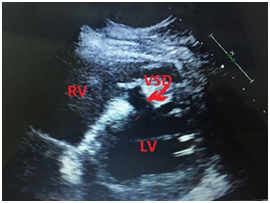

Coronary angiogram also showed 3 coronary vessel disease occluded mid LAD by thrombus at bifurcation with large diagonal so recanalized and stented LAD and postdilated properly. LV gram showed large ventricular septal defect VSD 14 x10 mm in anterior septal wall with tunal shape associated with significant left to right shunt (Figure 2A & 2B).

Figure 2A LV angiogram showing large VSD.

Figure 2B A-V loop throw VSD.

Patient deteriorated rapidly so intra-aortic balloon pump IABP and high doses of inotrops were started. We planned to closed this VSD by device in the catheterization laboratory on the same time but unfurtunalilly was did not have the suitable VSD dives size and No post MI device at all. Patient was shifted to cardiac intensive care unit for close observation and continue on inotrops, IABP and ventilation waiting for the suitable device. He remined stable slightly and after 5 days we prepared for post MI device closure since we obtained post MI VSD devices. The procedure was done under general anesthesia since the patients sedated and Trans jugular venous approach and femoral artery we created Arterio-venous loop (Figure 2) and throw 12 F sheath a 20 mm post MI VSD device closure was deployed successfully in place according to VSD device closure techniq under the guidance of trans-esophageal echocardiography and fluoroscopy (Figure 3).